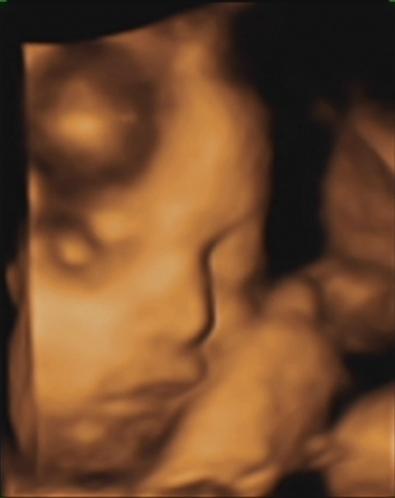

wczoraj nie miałam już siły, było 2,5 godz opóźnienia. Najważniejsze, że wszystko jest w porządku. Mała waży 1360 g, nadal jest kobietką, co bardzo chętnie pokazywałaJest już ułożona główką w dół i się raczej nie przekręci bo nie ma na to miejsca, zdj niestety nie ma bo jest już za ciasno i ciężko ją uchwycić. Widzieliśmy jak mała mrugała oczkami, lekarz nam kilka razy cofał nagranie-boskie to było

aaa i widzieliśmy coś jeszcze...nie zgadniecie co?... ona ma już włosy, tak dobrze czytacie włosy![]()